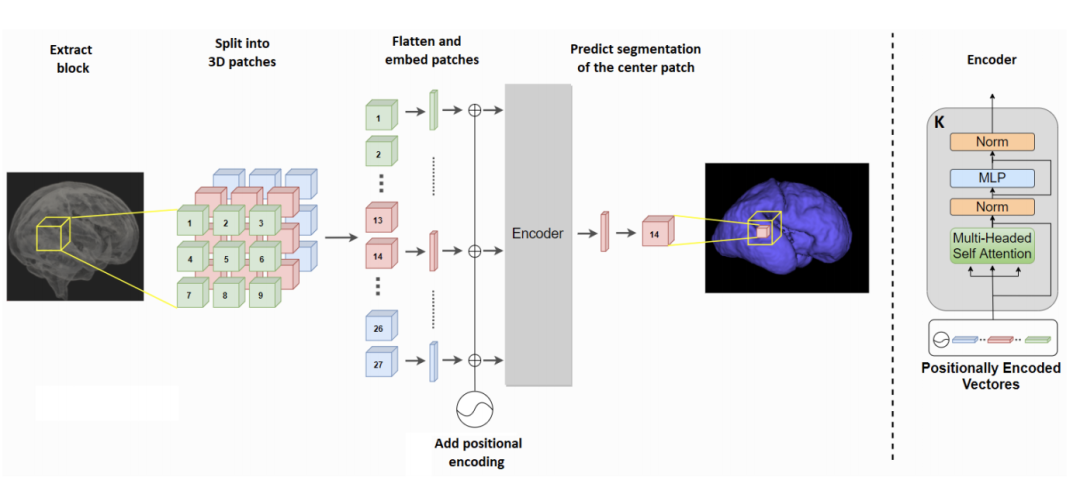

《Transunet: Transformers make strong encoders for medical image segmentation》

《CoTr: Efficiently Bridging CNN and Transformer for 3D Medical Image Segmentation》

《Convolution-Free Medical Image Segmentation using Transformers》

《Transfuse: Fusing transformers and cnns for medical image segmentation》

《Medical Transformer: Gated Axial-Attention for Medical Image Segmentation》

《Medical Image Segmentation Using Squeeze-and-Expansion Transformers》

《Multi-Compound Transformer for Accurate Biomedical Image Segmentation》

《UTNet: A Hybrid Transformer Architecture for Medical Image Segmentation》

《Mixed Transformer U-Net For Medical Image Segmentation》

《An Effective Medical Image Segmentation Transformer》

《T-AutoML: Automated Machine Learning for Lesion Segmentation using Transformers in 3D Medical Imaging》

《RTNet: Relation Transformer Network for Diabetic Retinopathy Multi-lesion Segmentation》